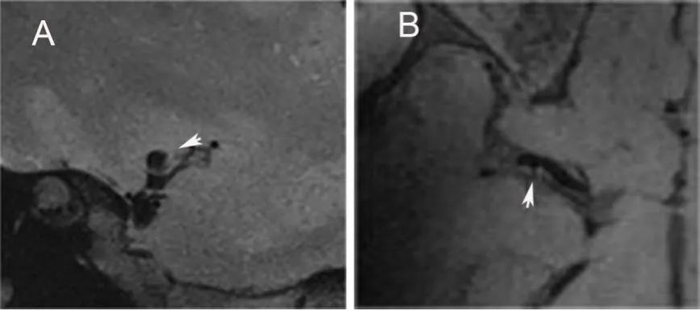

患者至西南医院神经内科就诊住院后左侧肢体麻木无力症状再次反复发作,经过缜密分析病史后,救治团队决定在发作期与发作间隙期分别进行头颅CTP检查,仔细读片后发现发作时右侧基底节区CBF较左侧下降(见图1)。为进一步明确患者脑血管病变情况,团队计划再行DSA脑血管造影并利用医院全球领先的7.0T核磁进行超高分辨率血管壁成像检查,经过仔细分析辨别讨论累计读片十余个小时后确定右侧大脑中动脉薄膜样增生突出管壁(见图2)。

图2. 7T高分辨血管壁成像显示患者右侧大脑中动脉管壁可见突出管壁的薄膜样增生不同研究显示隐源性(即原因不明的)卒中在青年缺血性卒中中的比例存在很大差异,约占5.9%到33%不等。颈动脉蹼(Carotid Web),又称颈动脉内膜型纤维肌发育不良,是颈内动脉少见的血管病变,是隐源性和复发性缺血性卒中的重要原因。这是一个少见病例,科室周振华主任指出,我们不能用常规思维来诊治该患者,尽管全球尚无类似病例报道,但颈动脉会出现“蹼”为什么大脑中动脉就不能出现?团队因此展开了热烈讨论,进一步调阅相关影像资料初步确定这有可能就是大脑中动脉蹼,并且真实世界中肯定不止这一例。